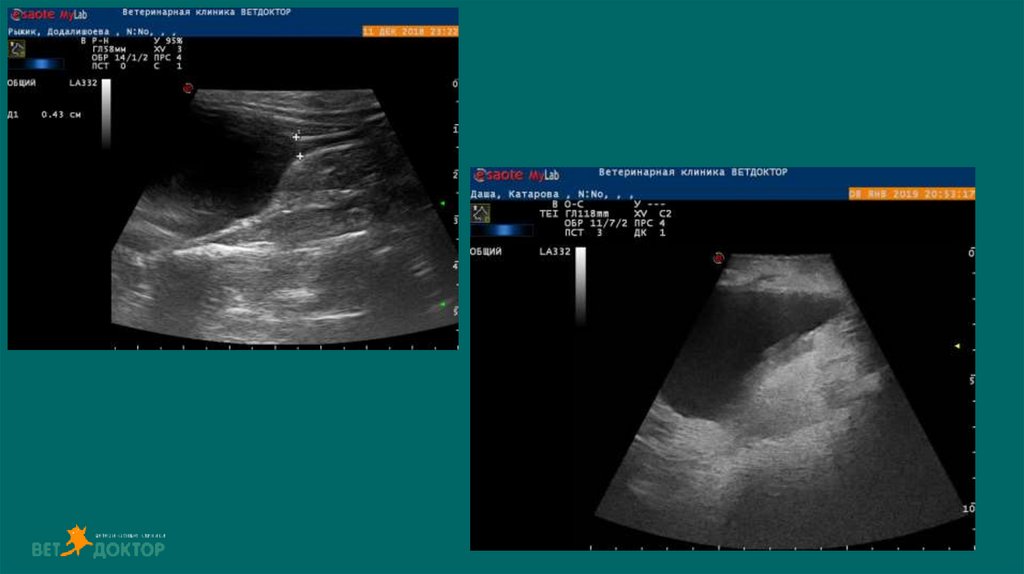

Можем обнаружить рентгенпрозрачные уролиты ,оценивать архитектуру

почки, паранефральные ткани, ретроперитониальные ткани, кисты

,инфартуи ы почек, изменение эхогенности, неоплазию, расширение

почечных лоханок и мочеточников, измерить толщину стенки мочевого

пузыря, визуализировать свободную жидкость в брюшной полости

УЗИ мониторинг изменений картины мочевой системы

• размер уретры

• размер лоханки и мочеточников

• количество свободной жидкости

38. УЗИ

Дилатация лоханки более 13 мм - обструкция

При диаметре лоханки более 8мм-высокая

вероятность обструкции